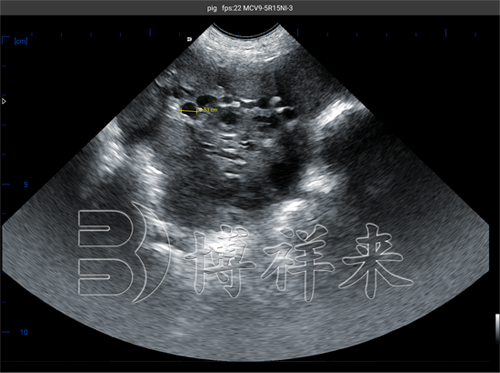

牛怀孕54天超声图像分析及诊断技巧

在养殖业中,通过超声波成像判断母牛的妊娠状态和胚胎健康情况,是常用且有效的方法。尤其在怀孕54天左右的阶段,了解牛胚胎的发育状况和超声图像的特点对胎儿存活率有重...